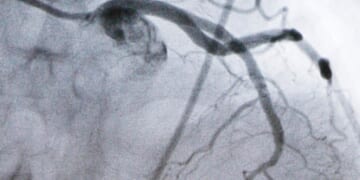

A new kind of pill sharply reduced artery-clogging cholesterol in people who…